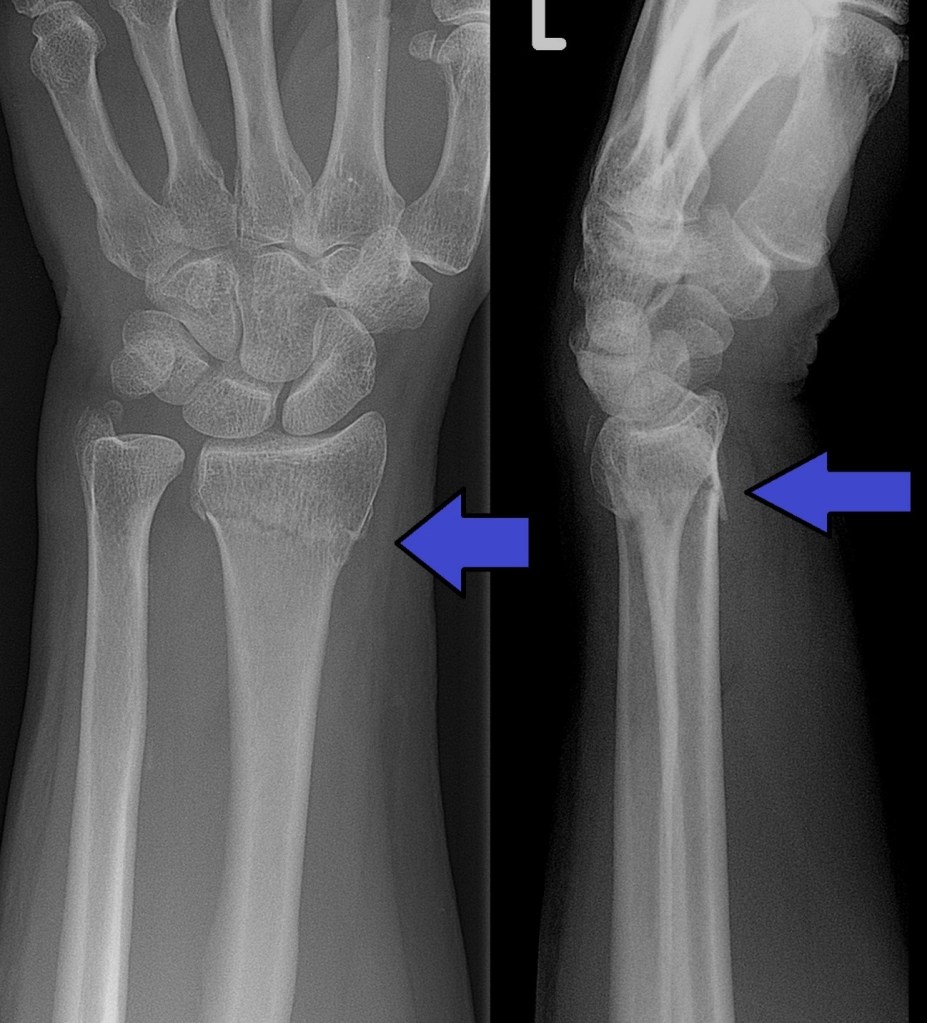

El 1811, publica “Teatrise of surgical anatomy” (Fig.3) i, el 1814, l’article en el que descriu la fractura que es coneix amb el seu nom (Fig.4), que es publica a l’Edimburg Medical and Surgical Journal amb el títol On the fracture of the carpal extremity of the radius. Aquesta fractura provoca un desplaçament dorsal característic amb angulació que adopta l’aspecte d’una forquilla (Fig.5). Cal destacar la precisió amb la que Colles descriu la fractura, sense disposar de raigs X.